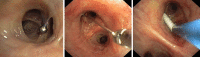

Endobronchial coils are an additional treatment option for lung volume reduction in patients with severe emphysema. Patient selection should be focused on patients with severe emphysema on optimal medical therapy and with evidence of severe hyperinflation. The technique is suitable in a broad range of patients with emphysema; however, patients with paraseptal emphysema, large focal (giant) bullae, significant co-morbidity and airway-predominant disease should be avoided. Treatment involves placing between 10 and 14 coils by bronchoscopy in the selected treatment lobe, with 2 lobes being treated sequentially. Lobe selection for treatment should be based on quantitative computed tomography, and the lobes with the greatest destruction should be targeted (excluding the right middle lobe). The treatment results in an improvement in pulmonary function, exercise performance and quality of life, particularly in patients with severe hyperinflation (residual volume > 200% predicted) and upper-lobe heterogeneous emphysema, but will also be of benefit in lower-lobe predominant and homogeneous emphysema. Finally, it has an acceptable safety profile, although special attention has to be paid to coil-associated opacity which is an inflammatory response that occurs in some patients treated with endobronchial coils.